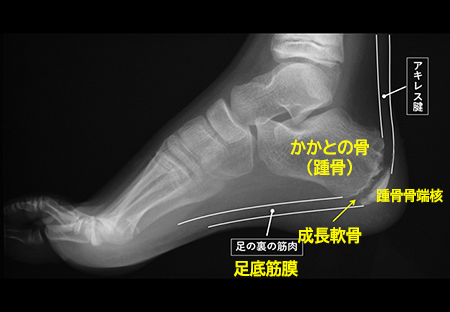

発育期の子どもの骨は、大人と違い、骨が成長していく部分(骨端線あるいは成長軟骨と言います)が残っています。(下図の矢印)

骨端線は物理的に弱く、かかと部分の骨(踵骨)には、アキレス腱と足の裏の筋肉がついているため、運動で繰り返し骨端線の周囲にひっぱる力が加わることで、炎症を起こしたり、骨に細かい傷がついたりすることが痛みの原因と言われています。

レントゲン検査で、骨端線よりも外側の部分の骨(骨端核)が他の部分にくらべて白くなっていたり(骨硬化)、いくつかの骨に分かれていたりする(分節化)などの変形があるか等を確認します。